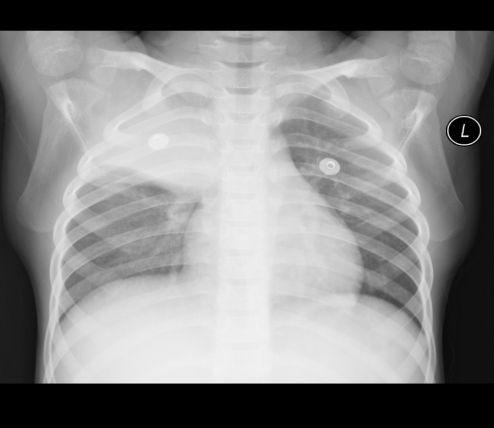

胸片爆料2025年最新版

你有没有听说?2025年的胸片爆料来啦!没错,就是那个能让你一窥未来科技风采的胸片。今天,就让我带你从多个角度来揭秘这个神秘的新版胸片,让你大饱眼福!一、外观升级,科技感十足首先,让我们来看看外观。2025年的胸片在造型上可谓是下足了功夫。采用了流线型的设计,线条流畅,给人一种未来科技的感觉。而且,这款胸片采用了全新的材质,不仅轻便舒适,还具有良好的透气性。穿上它,仿佛置身于未来科技的世界。二、功